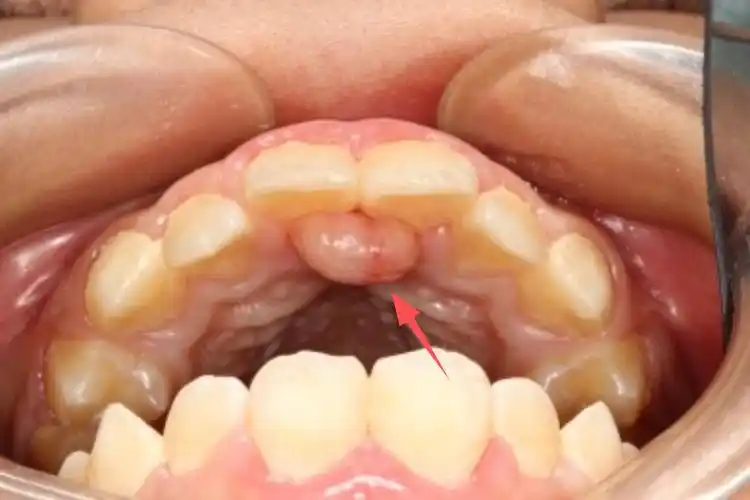

宝宝13个月.上牙的里边又长了一个硬硬的白色的东西.

孩子长了双排牙怎么办别急简单两步马上搞定

7岁孩子乳牙一颗没掉,也没有一点松动,从下牙床内

二牙龈疾病